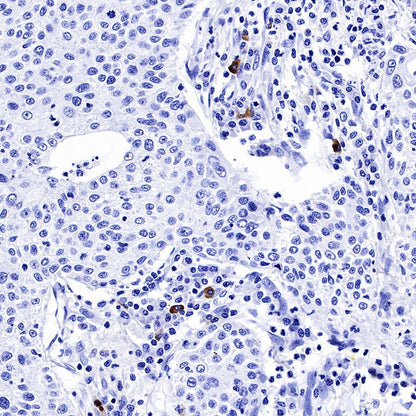

IHC shows positive staining in paraffin-embedded human lung squamous cell carcinoma. Anti-IGJ antibody was used at 1/1600 dilution, followed by a HRP Polymer for Mouse & Rabbit IgG (ready to use). Counterstained with hematoxylin. Heat mediated antigen retrieval with Tris/EDTA buffer pH9.0 was performed before commencing with IHC staining protocol.